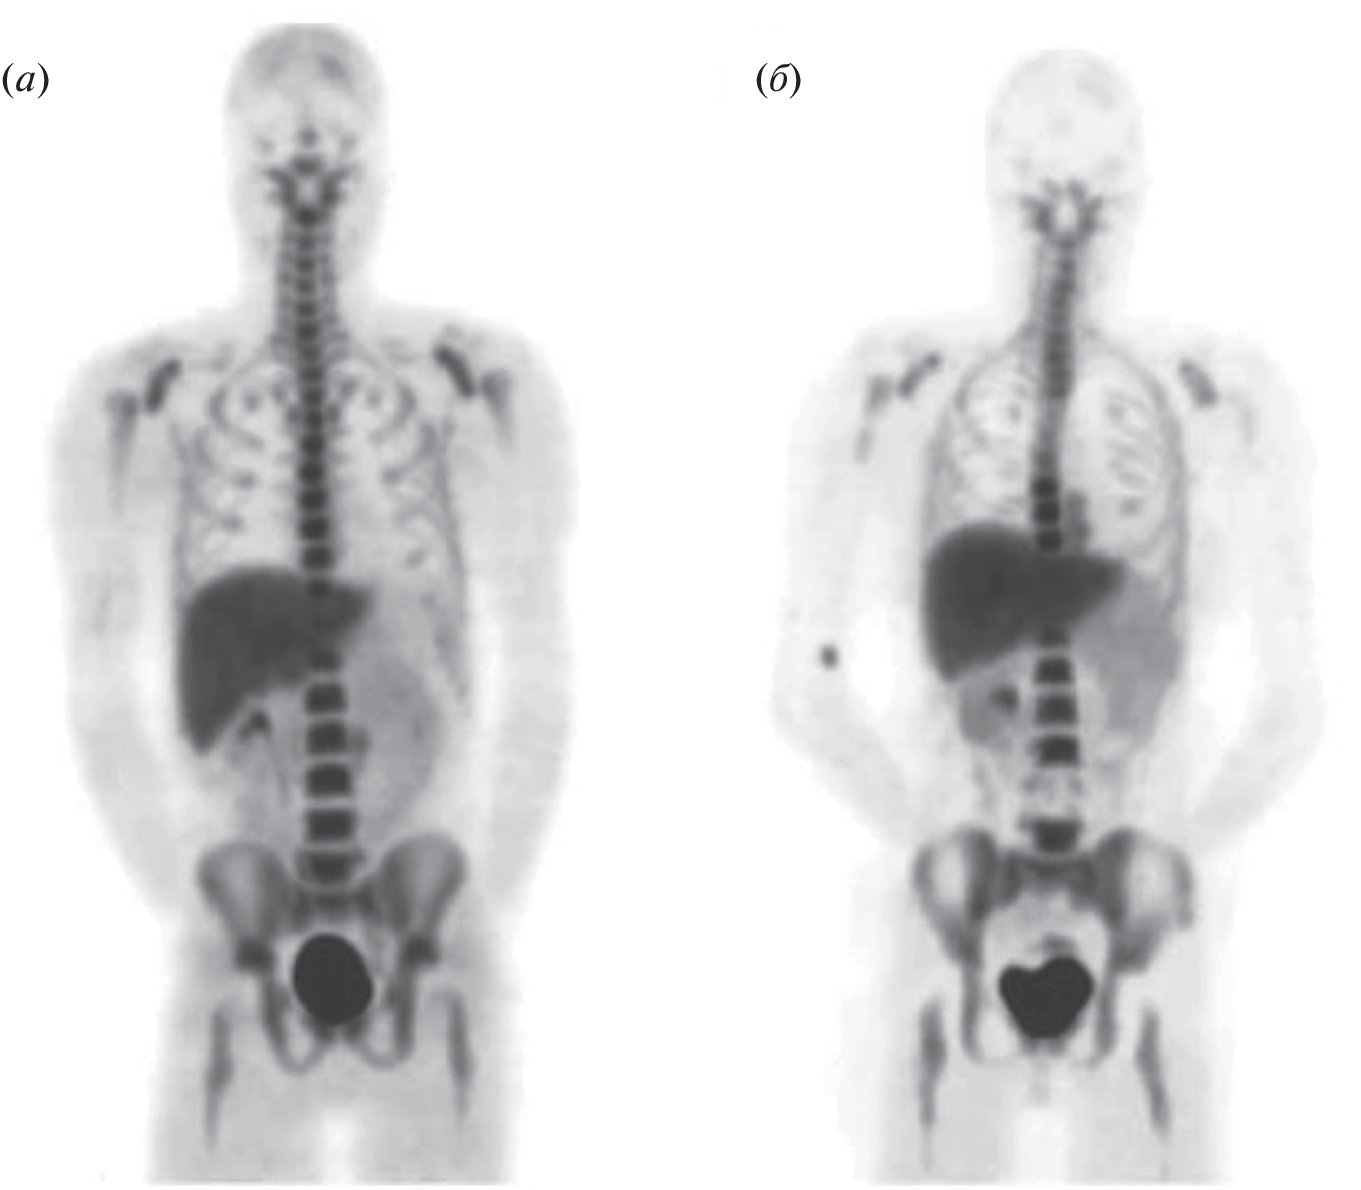

- Agool A., Glaudemans A.W.J.M., Boersma H.H., Dierckx R.A.J.O., Edo Vellenga E., Slart R.H.J.A // Eur. J. Nuclear Med. Mol. Imaging. 2011. V. 38. P. 166–178. https://doi.org/10.1007/s00259-010-1531-0